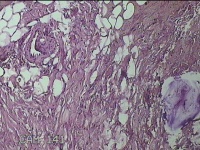

左侧会阴部皮下结节

性别

女

年龄

45岁

临床诊断

皮下结节

一般病史

发现左侧会阴部皮下结节2年余,伴近日局部隐痛不适。

标本名称

大体所见

灰白暗红色结节0.8x0.7x0.3cm一个,表面糜烂。

图2